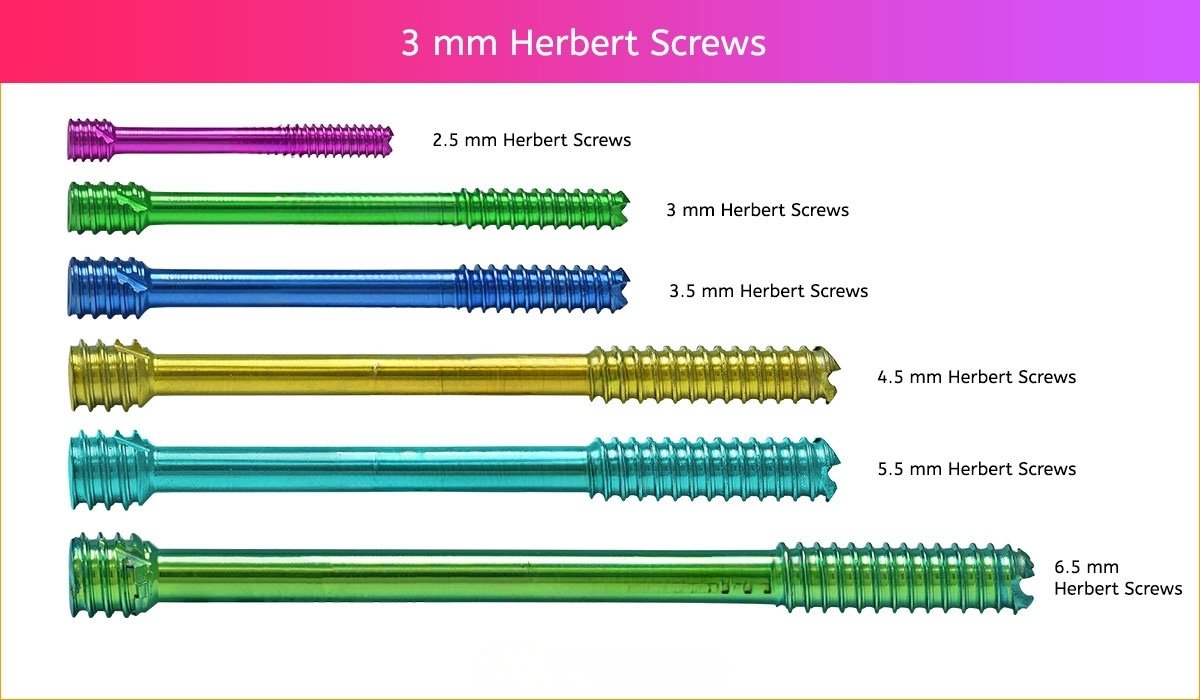

3 mm Herbert Screw

3 mm Screws Length

8mm, 10mm, 12mm, 14mm, 16mm, 18mm, 20mm, 22mm, 24mm, 26mm, 28mm and 30mm.

- 2.5 mm and 3 mm Herbert Screws are indicated for fixation of fractures and nonunions of small bones and small bone arthrodeses, including scaphoid fractures; intraarticular fractures of the tarsals, metatarsals, carpals and metacarpals; bunionectomies and osteotomies; arthrodeses of small joints (e.g. phalanges); fractures of the patella, ulna and radial styloid.